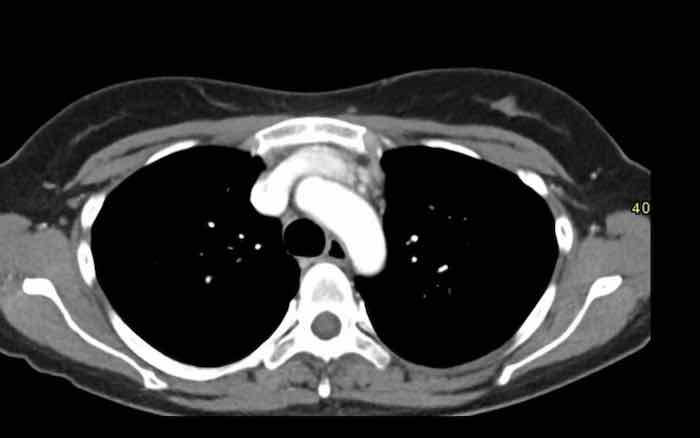

Các hình ảnh này của một nam giới 19 tuổi, được chụp CT để loại trừ thuyên tắc phổi.

Phát hiện tình cờ một khối ở khoang trước mạch máu.

Chẩn đoán có khả năng nhất là tăng sản tuyến ức và MRI được thực hiện để phân biệt thêm khối này.

Trên hình ảnh chuỗi xung T2W, tổn thương có tín hiệu tăng nhẹ.

Trên hình ảnh pha đối (out-of-phase), không có sự sụt giảm tín hiệu đáng kể.

SII nhỏ hơn 9%.

Do bệnh nhân không có bất kỳ triệu chứng nào, đặc biệt không có các triệu chứng có thể liên quan đến u lympho, và vì u tuyến ức (thymoma) là một khối u hiếm gặp, quyết định được đưa ra là theo dõi sau sáu tháng.

Tại thời điểm theo dõi sáu tháng, tuyến ức có hình ảnh bình thường.

Kết luận được đưa ra là đây là tăng sản tuyến ức hoặc mô tuyến ức tồn dư kích thước lớn, đã thoái triển trong vòng sáu tháng.